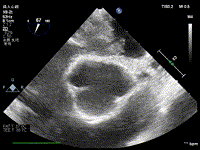

62岁的李先生8周前突然晕倒不省人事,紧急送至我院神经内科,行头颅磁共振检查发现多发性脑梗死(双侧丘脑,小脑半球、脑桥等多处病灶),急诊行脑血管造影却未见明显颈部及颅内血管狭窄病变,患者昏迷数日后方苏醒,但出现了言语及认知障碍、吞咽困难等后遗症,在积极康复治疗的同时,经过仔细检查,终于发现了导致患者发生脑梗死的元凶。心脏超声检查在患者的左心房内发现了一个巨大的肿物,约5cm×3cm大小,附着于房间隔上,随着心跳翩翩摆动,穿梭于二尖瓣口。根据心房内肿物的影像学表现,临床推断其为左心房粘液瘤,其脱落的瘤体组织进入了脑血管导致了多发性的脑梗死。

心脏粘液瘤是临床中最为常见的心脏良性肿瘤,多见于中年时期,女性多于男性。心脏粘液瘤可发生于心脏所有的心内膜面,其中约 75% 位于左心房,20% 位于右心房,5% 发生于心室。心房粘液瘤中最常见的起源是房间隔,粘液瘤的“根部”(瘤蒂)与房间隔相连,瘤体呈松脆的胶冻状,可随心脏跳动在心腔内摆动。粘液瘤的瘤体碎片以及瘤体表面附着的血栓极易脱落,心脏粘液瘤最常见的并发症即是栓塞并发症,是导致心源性脑梗死的常见元凶之一。另外,巨大的瘤体也可产生心腔内梗阻及心衰表现,瘤体堵塞二尖瓣口,可导致晕厥、甚至猝死的严重后果。尽早施行手术切除是心脏粘液瘤治疗及预防其产生严重后果的唯一办法。